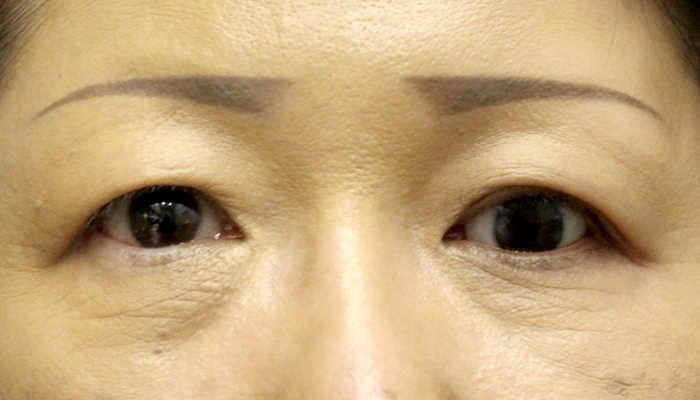

症例3

| 術前 | 左無眼球症、眼球陥凹 |

|---|---|

| 術後 | 左義眼台包埋術後 |

| 治療費 | 準備中 |

| 治療のリスク | 腫れが引かない、内出血がある、目が閉じにくい、完全に閉じないなどのリスクがあります |